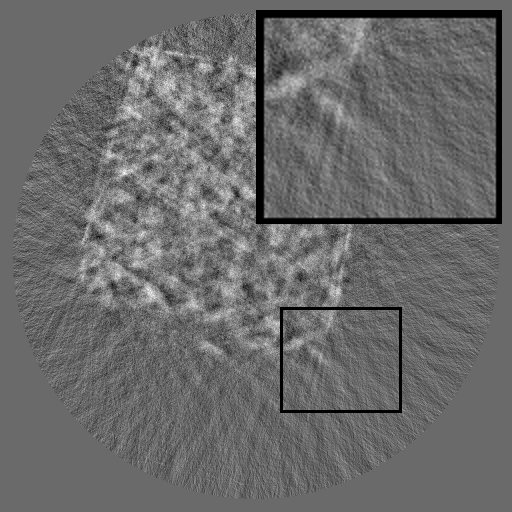

Refer to caption

(a) RGB Img

(b) RGB Spec

(c) Sino Img

(d) Sino Spec

Figure 1: Comparisons of RGB and sinogram and their spectra. Unlike RGB images, which have localized frequency components, sinograms exhibit structured spectral distributions due to the Radon transform.

Unfortunately, most existing inpainting methods are developed for RGB images [liu2024structure, zhang2023coherent, ko2023continuously, deng2022hourglass, lugmayr2022repaint, li2022misf, suvorov2022resolution], where missing regions can be locally inferred from surrounding pixels. However, such spatial assumptions fail in X-ray sinograms, where each pixel represents an integrated projection value along an X-ray path, causing globally entangled structures. Several studies have explored sinogram completion using U-Net- [zhao2018unsupervised, yao2024no], GAN- [valat2023sinogram, xie2022limited] or Transformer-based [jiaze2025sinotx] models, and some have incorporated periodicity or reconstruction-based constraints [li2019sinogram, wagner2023geometric]. However, these methods remain largely spatial, focusing on pixel-wise interpolation or appearance realism, and fail to explicitly model the structured frequency domain or the governing physics of sinogram formation, which are fundamentally distinct from those of RGB images. As defined by the Radon transform [radon_uber_1917], the detector and angle axes of a sinogram represent distinct physical dimensions, leading to highly directional and asymmetric spectral patterns (see Figure 1). Recognizing these unique characteristics, we design a framework FCDM that explicitly leverages both the frequency-domain organization and physical consistency of sinograms for faithful and coherent restoration.